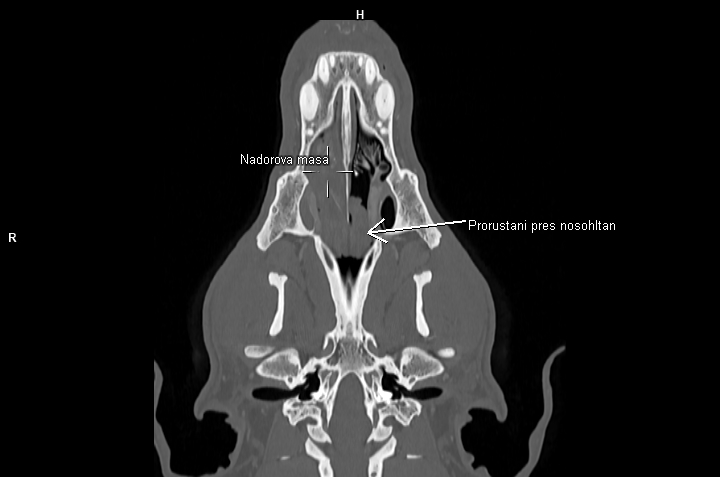

Nedílnou součástí diagnostiky ve veterinární onkologii se tak stává CT vyšetření. Velká spirální CT spolu s použitím kontrastní látky nám umožňují velmi detailní zobrazení i hlubokých struktur těla, stav okolních měkkých tkání, průběh velkých cév v bezprostředním okolí a přítomnost metastáz. Lze pak mnohem přesněji cíleně odebrat bioptické či cytologické vzorky z patologické tkáně, určit operabilnost nádoru a v případě nálezu metastatického rozsevu zvážit další postup (chemoterapie, ozařování atp.)

Jednou z oblastí, které na klinice Medipet nejčastěji pomocí computerové tomografie vyšetřujeme, je hlava a krk.

- nádory dutin nosních.